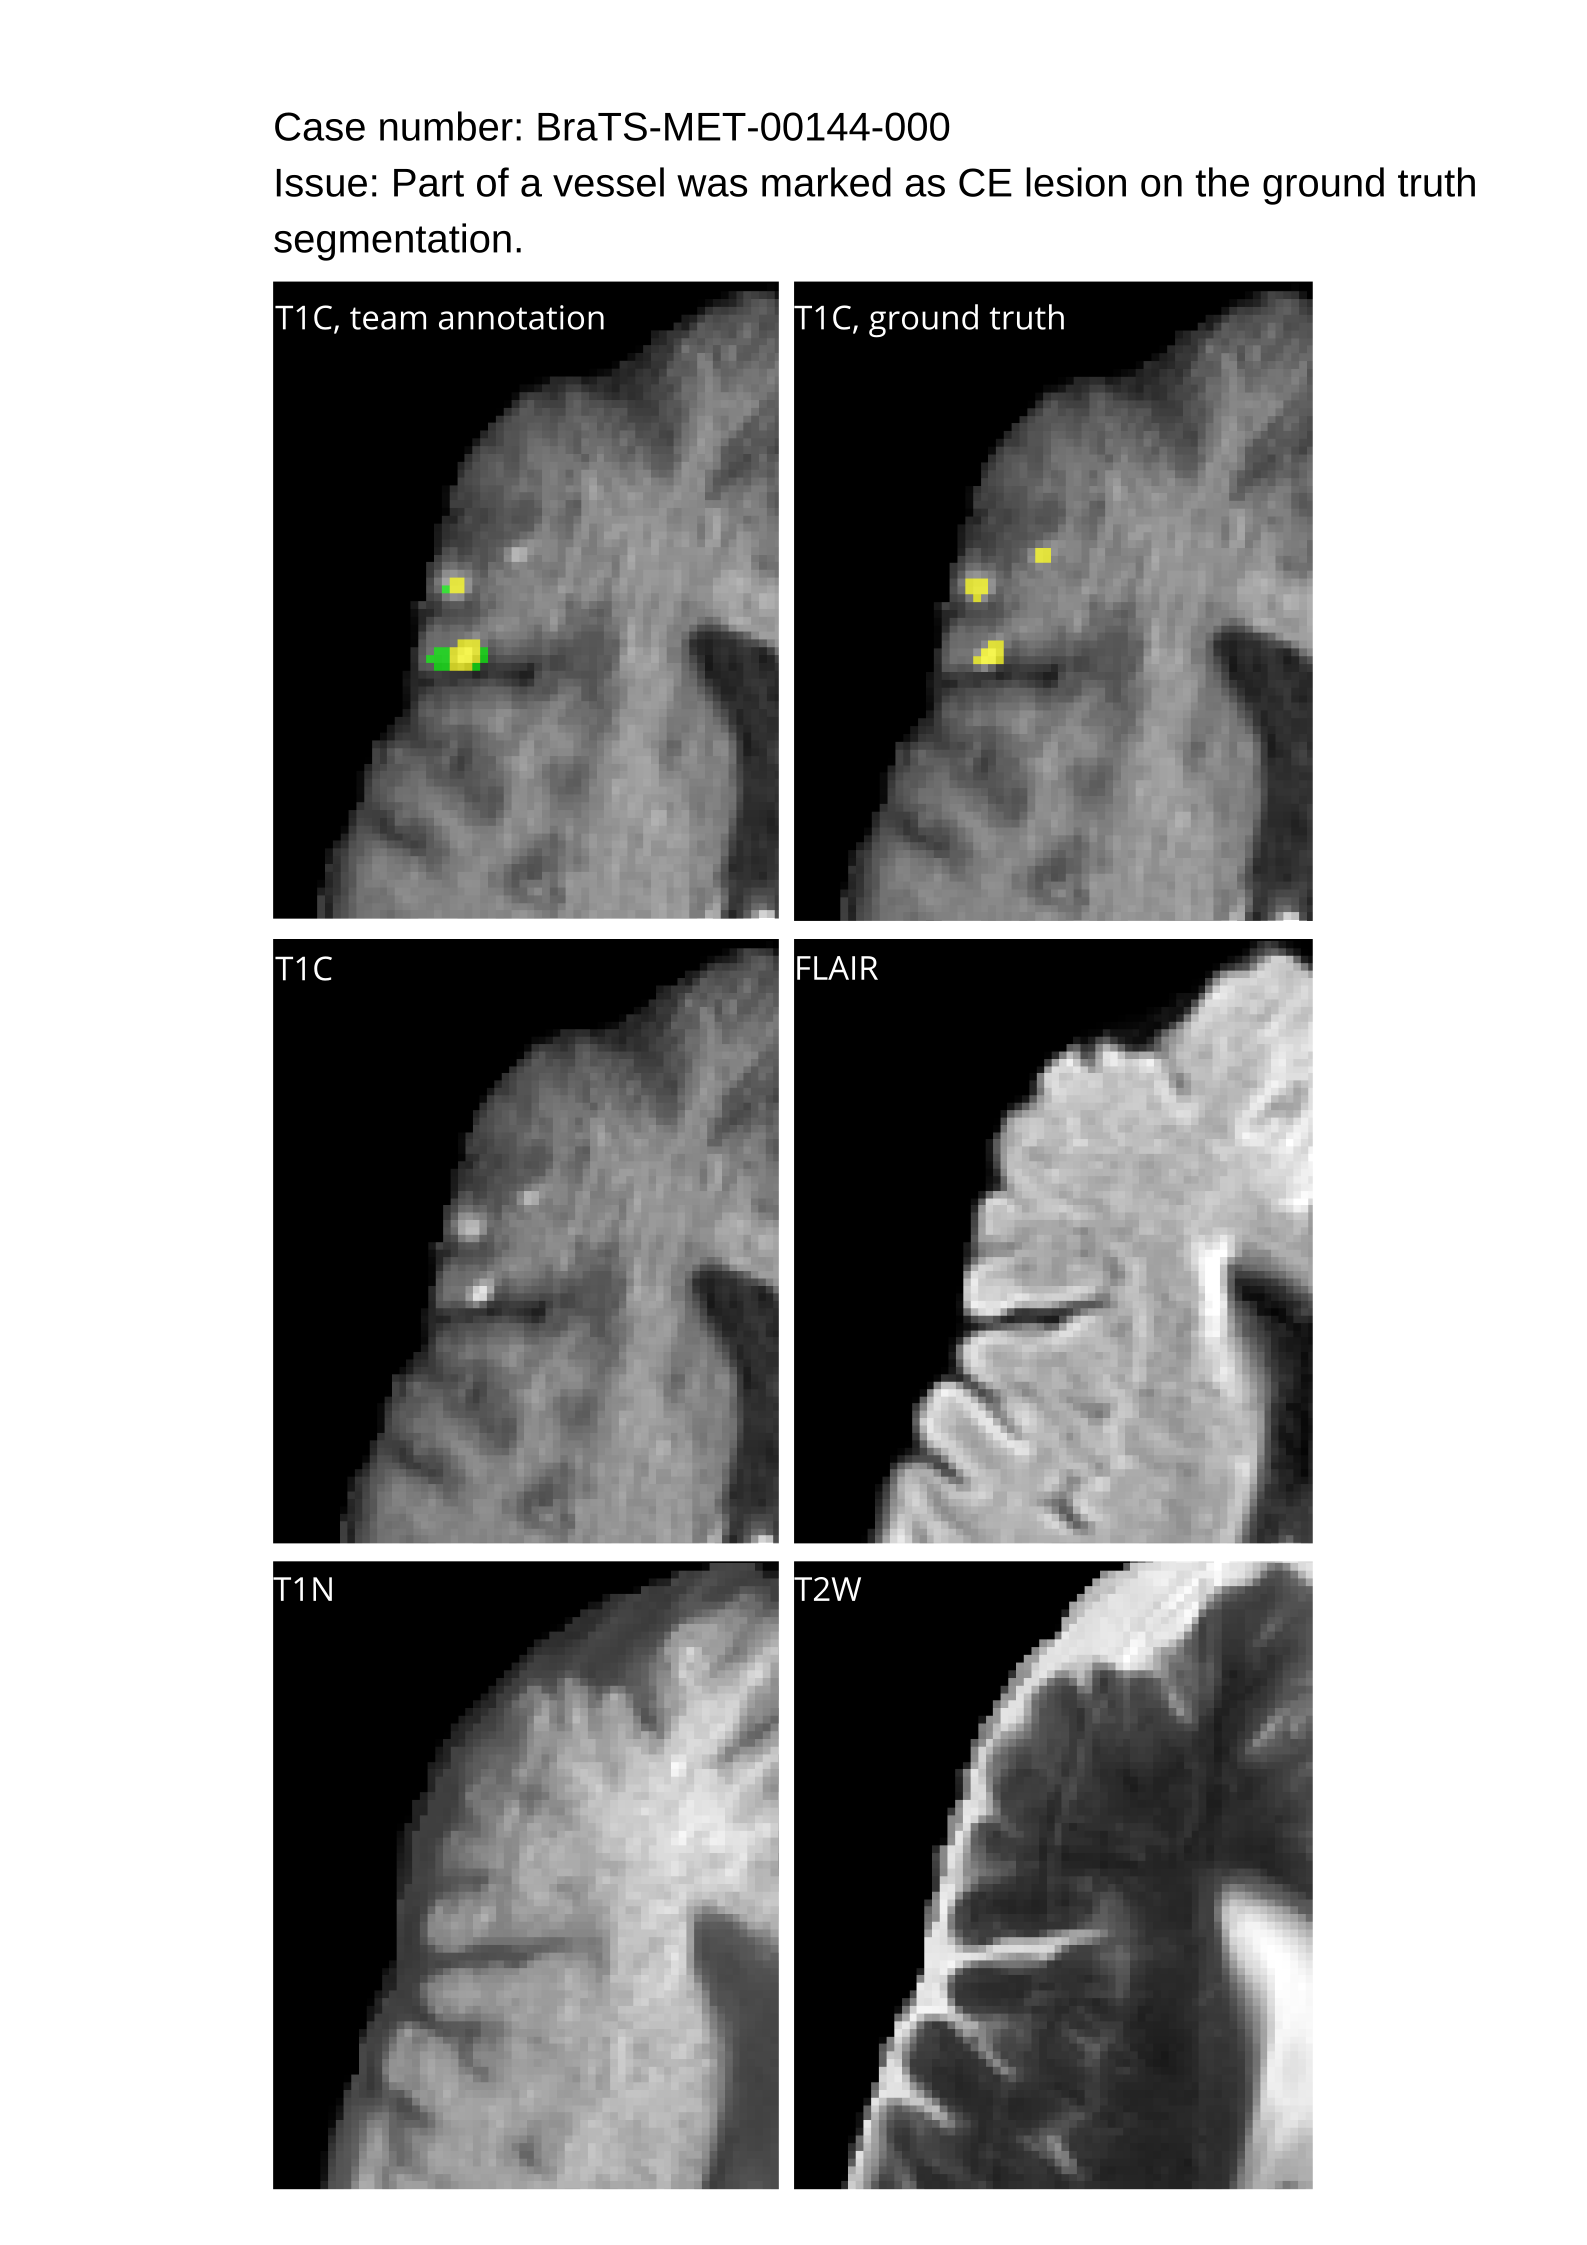

Approvers reviewed the volunteer annotations and either approved the case or returned it to students for re-annotation. Additionally, a QC process was implemented, which included removing all random voxels and any voxels outside the brain mask, ensuring all images had the same parameters (space, orientation, and origin) as the SRI24 atlas, and verifying the presence of all segmentations and segmentation masks are in the folder with original NIfTI images.

Acknowledging the variability in lesion significance arising due to human error, a volumetric threshold of 2 voxels (2 mm3superscriptmm3\text{mm}^{3}mm start_POSTSUPERSCRIPT 3 end_POSTSUPERSCRIPT) was established by an expert panel of clinical radiologists, below which the models’ performance on deemed ”small/false” lesions is not considered in the evaluation. This approach was primarily adopted to ensure that participants were not unfairly penalized for stray voxels in the GT labels, which may result from human error, or for small lesions unrelated to the pathology central to the challenge. The expert panel of clinical radiologists also determined the dilation factor, which was uniformly applied for combining lesions in the GT masks. A dilation factor of 1 voxel in 3D space was chosen because BMs can be small, and it is important to avoid combining these small BMs.